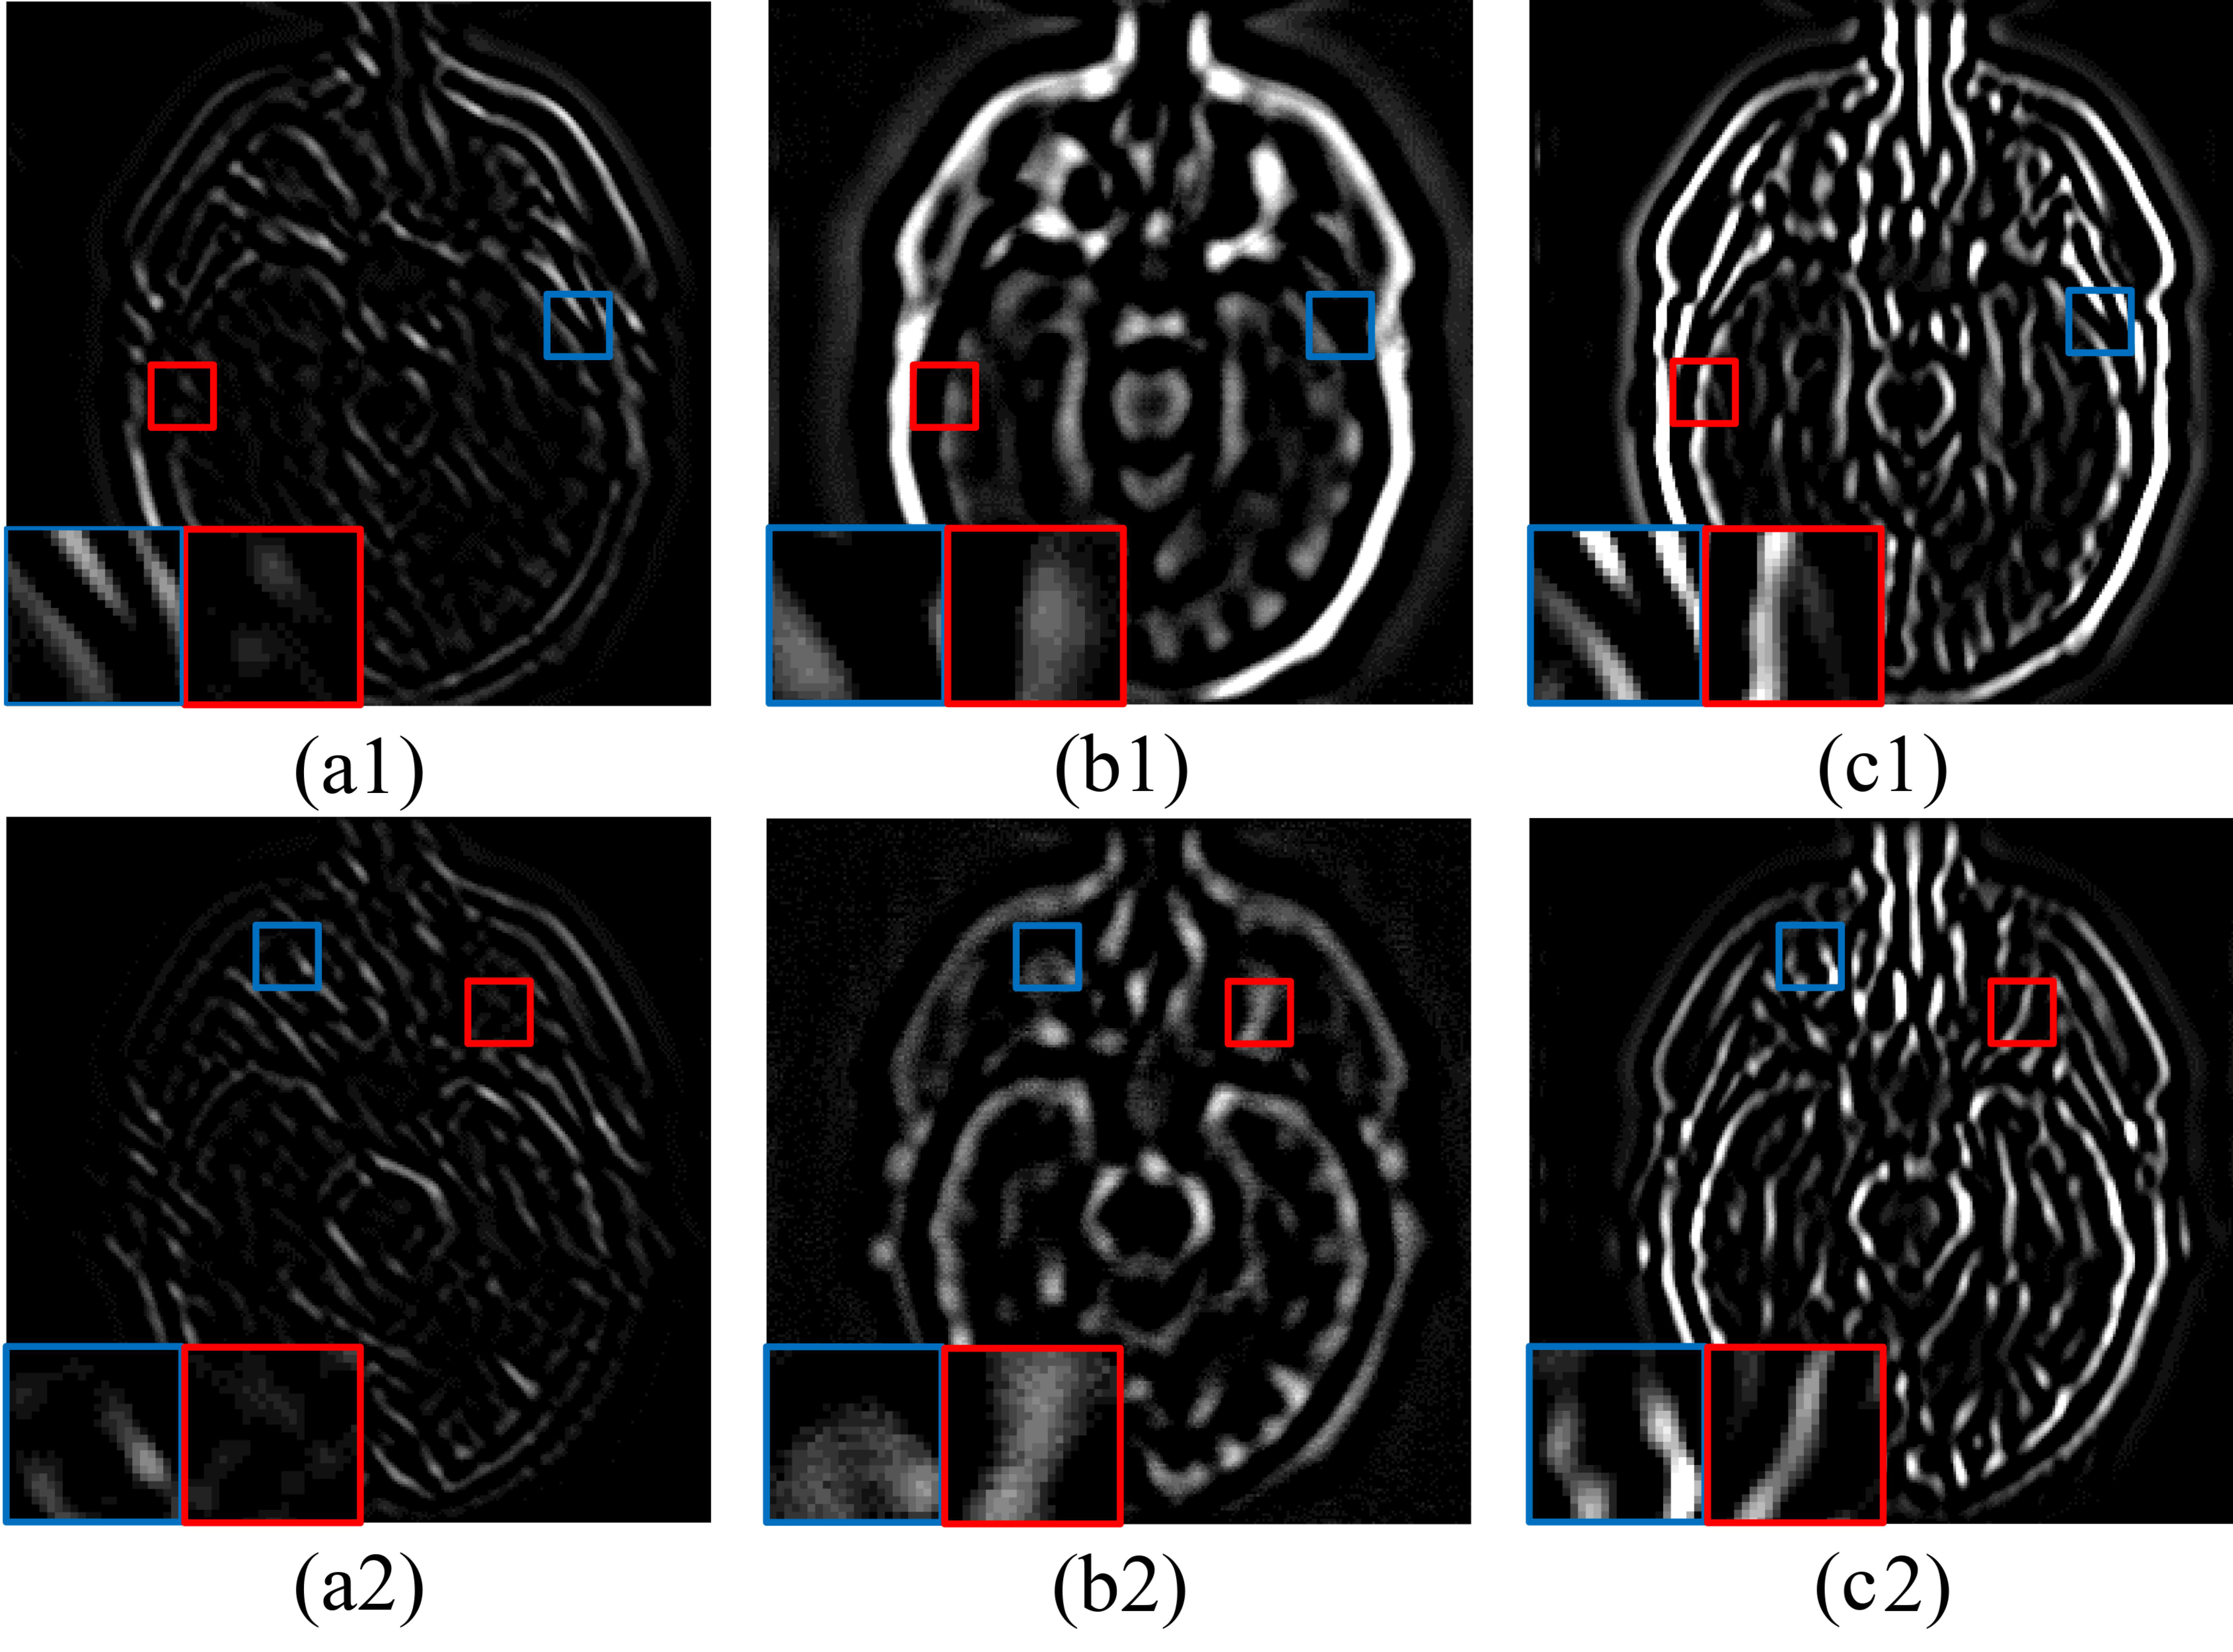

4.2. Tensor Decomposition Based Fusion

4.4. High-Frequency Completion

4.4.1. Joint Static and Dynamic Guidance

4.4.2. Fusion of Complete Mixed-Frequency Maps